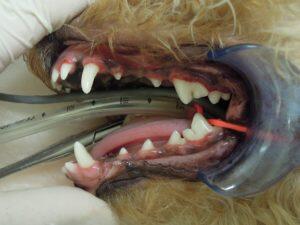

7.ポリッシングを行い、治療終了です。

8.治療後の右側外観です。

9.治療後の左側外観です。

歯肉炎や軽度歯周炎であれば、特別な歯周外科治療でなく、一般的なスケーリング処置で状態の改善が認められます。

術後ご自宅での口腔内ケアを指導させていただいて、定期的な歯科検診で良い状態を維持します。